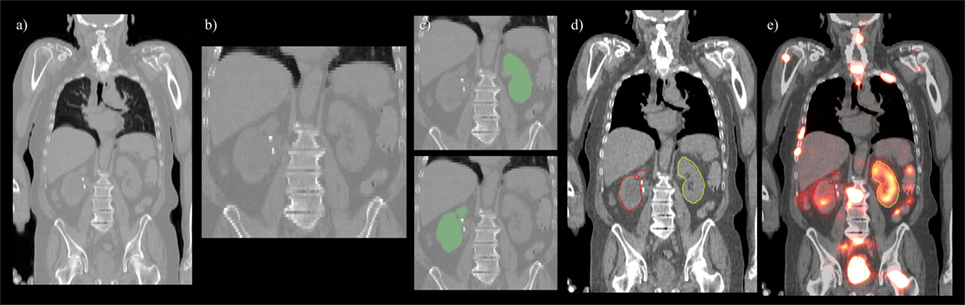

Convolutional neural network input volume is a matrix with dimensions 128 × 128 × 64 voxels. The workflow involved several pre-processing steps. First, bony anatomy was aligned with a reference patient by rigid registration (22). Images were cropped to a smaller search volume of 334 × mm x 334 × mm x 320 mm; a volume that could consistently capture the variation in kidney location between patients, while limiting the degree of downsampling required for input into the CNN algorithm. The native hybrid CT voxel resolution of 0.98 mm × 0.98 mm × 5.0 mm was subsequently resampled at 2.61 mm × 2.61 mm × 5.0 mm to achieve the required matrix dimensions. The complete workflow is illustrated in Figure 2. All training patients were pre-processed by the same methodology. Network training was allowed to run for 300 epochs using 640 teaching subjects. Another 72 augmented samples were used as a semi-independent scoring set to test training progress. Processing required 2.5 days on a cuda-enabled GPU (Nvidia GeForce GTX 1080 Ti) achieving dice accuracy of 0.98 with training data and 0.93 with a subset of augmented training patients as shown in Figure 3.

Figure 2. Pre- and post-processing workflow developed for automated renal dosimetry. Input image (A) is automatically cropped to a smaller search area based on alignment to a reference image volume. The cropped and downsampled image (B), 128 × 128 × 64 voxels, is used as input to the convolutional neural networks segmentation model. Labeled left and right kidneys (C) are then upsampled, smoothed, and fused with the original, uncropped image (D). Label map is exported in dicom-RT structure file, where voxel dose images may be analyzed on a hospital workstation (E).

Figure 3. Evolution of model accuracy with over the 300 epochs for the training cohort (blue) and an augmented testing cohort (orange). Training required approximately 2.5 days for completion.